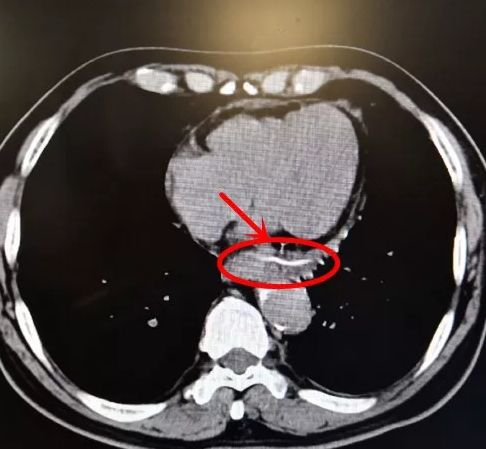

1个月前,陈老伯的疼痛越发明显,在外院做CT检查后提示食管中段有横行线样致密影,且局部与主动脉弓分界不清,不排除有异物的可能性。

12月18日下午,一场紧张凶险的“拆弹战”打响了。术中见食管中部有一个肉芽肿隆起突出部位,“根据经验和CT片判断这就是异物所在位置!”周教授用钩刀在肉芽肿口侧轻轻划开,逐步切割瘢痕,一个黑色金属异物影逐渐显露,但CT提示异物与主动脉弓分界不清,这给手术造成了巨大的难度。周教授用异物钳小心取出异物,反复观察食管伤口没有丝毫出血。